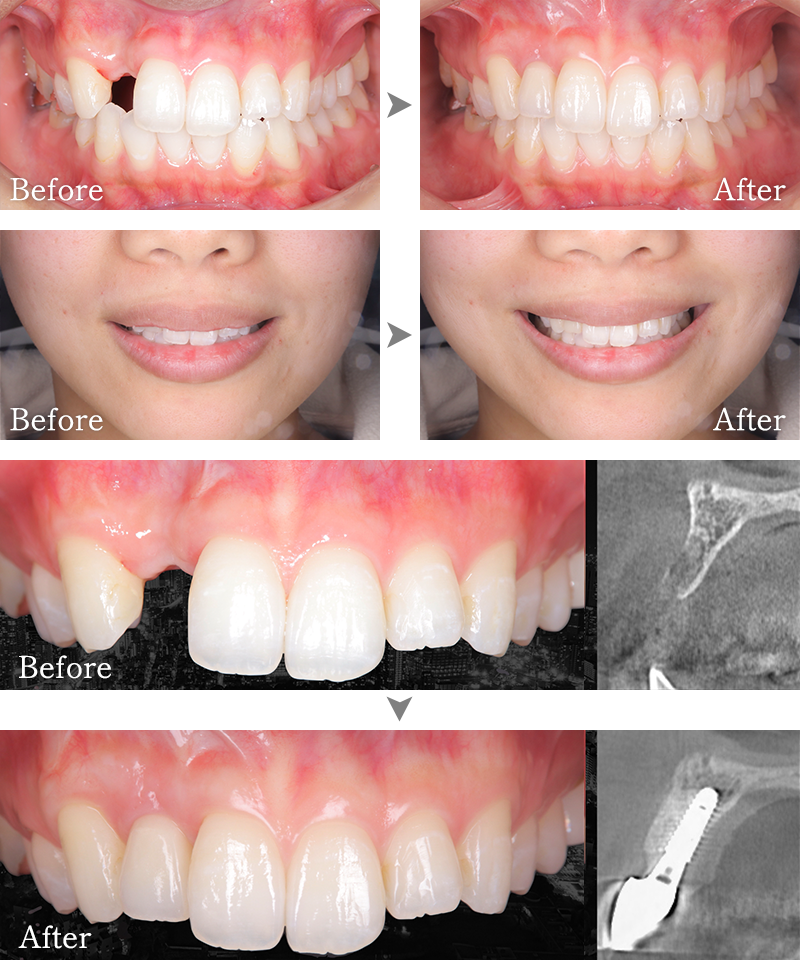

CASE4

主訴 右側でうまく噛めない

治療内容 下顎臼歯部インプラント、咬合再構成、上顎矯正治療、セラミック治療

治療期間 約2年

費用 診断料:22万円(税込)

下顎顎臼歯部インプラント埋入手術:22万円(税込)×4本

セラミック補綴:22万円(税込)×4本

セラミック治療:11万円(税込)×9本

矯正治療:44万円(税込)